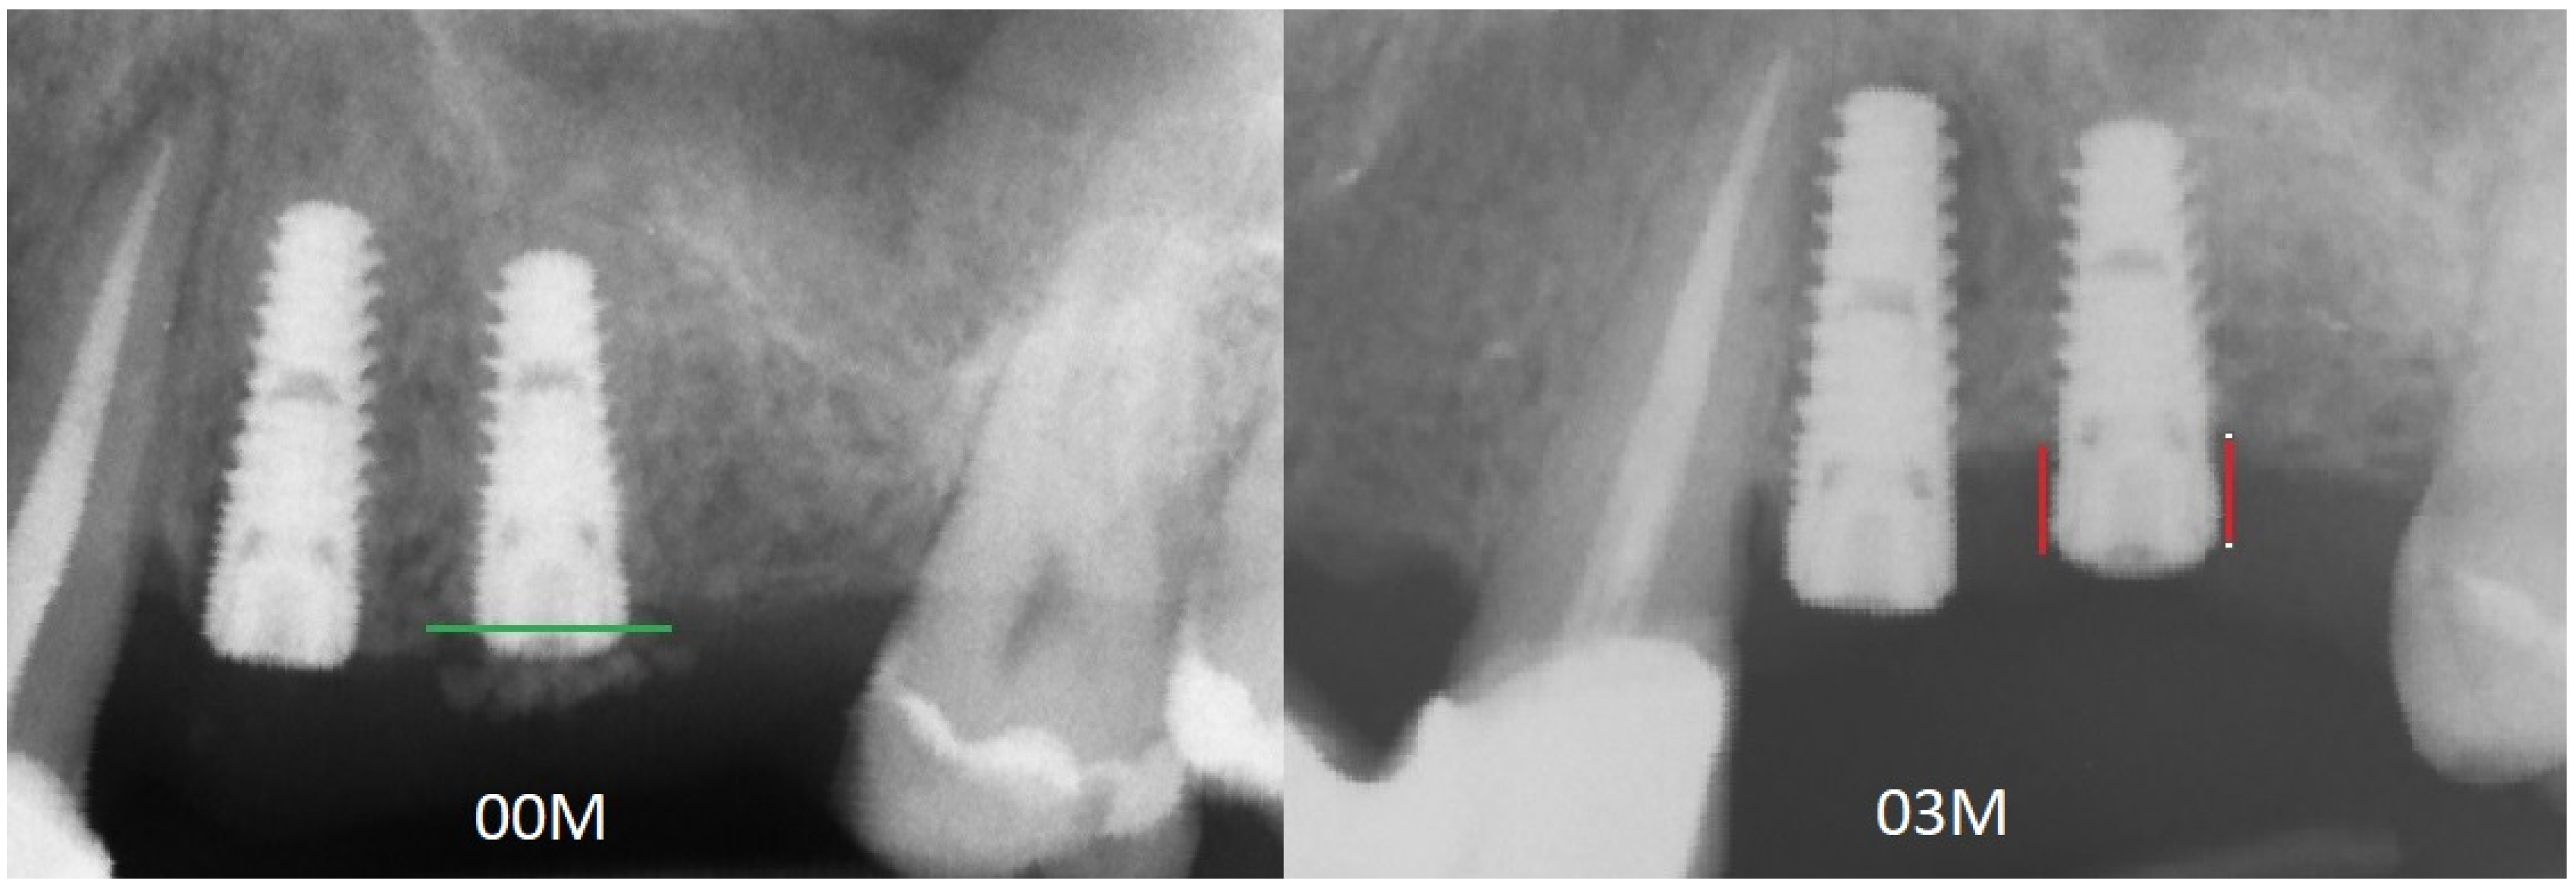

2. Materials and Methods

- MBL appearance (YES) if MLB is >0

- MBL appearance (NO) if MBL is =0